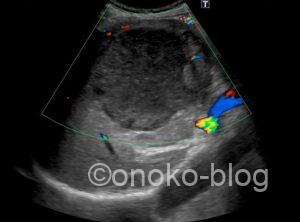

他の症例画像です

(少し大きさは違いますが)

最近発熱はなかったとの事でしたが、エコー所見から

肝膿瘍の疑いで報告書を提出し、他院紹介。

精査の結果アメーバ性肝膿瘍の診断とのお返事をいただきました。

アメーバ性肝膿瘍は単発で、右葉に多いそうです。

病期によってエコー所見が違うのも特徴ですよね。

(過去の症例もアメーバ性肝膿瘍でした)